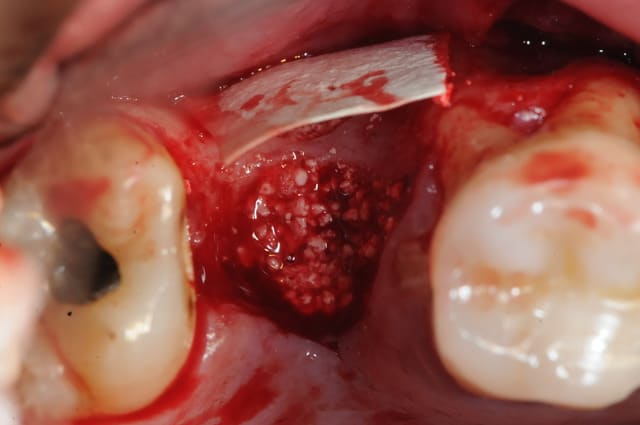

1&2 : réalisation à l'aide d'une tréphine de la fenêtre vestibulaire pour aller plus vite et surtout pour pouvoir réutiliser plus tard ce petit bloc osseux.

( vous verrez plus atrd à quoi ça sert)

3: fenêtre et CBS bien visibles

j'aurai aimé faire mon abord latéral plus haut, mais je vous rappel que l'on est au niveau de la 7 et que c'est difficile d'écarter les tissus.

(Rachel qui m'a gentiment assisté à beaucoup souffert de tétanisation musculo-palmaire multiple)

vous noterez tout de suite la différence de teinte entre un sinus sain et avec ici, un sinus hyper inflammatoire et infecté (une vraie cocotte-minute)